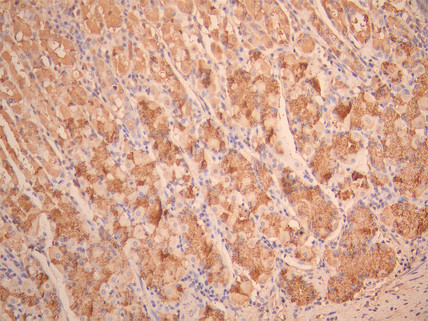

IHC image of CSB-RA025342MA1HU diluted at 1:50 and staining in paraffin-embedded human stomach tissue performed on a Leica BondTM system. After dewaxing and hydration, antigen retrieval was mediated by high pressure in a citrate buffer (pH 6.0). Section was blocked with 10% normal goat serum 30min at RT. Then primary antibody (1% BSA) was incubated at 4°C overnight. The primary is detected by a Anti-Human lgG, Fcy Fragment Specific labeled by HRP and visualized using 0.05% DAB.

Immunohistochemistry analysis of paraffin-embedded human lung carcinoma tissue using TUFM antibody.